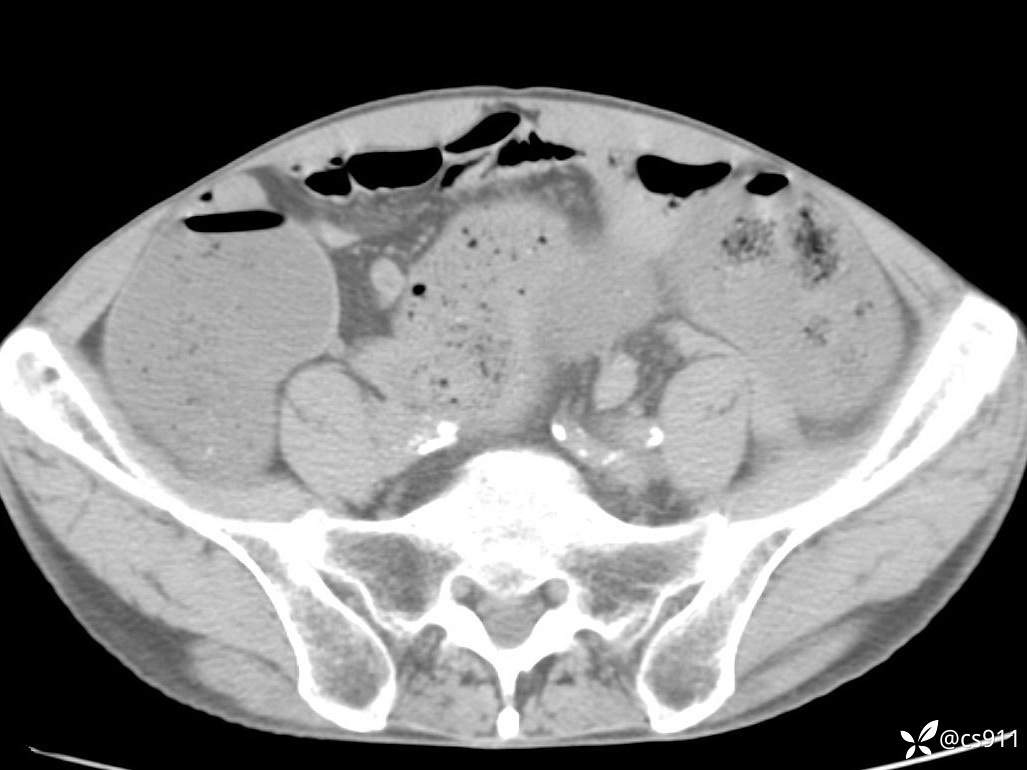

急腹症之急诊CT,原因?答案公布

男,77岁,腹痛、腹胀伴恶心呕吐1天。呕吐胃内容物,非喷射性呕吐,有咖啡色样胃内容物,诉有胃穿孔病史。查体:全腹平,下腹部压痛,全腹无反跳痛,叩诊呈浊音,移动性浊音阴性,肠鸣音减弱,1-2次/分。肛检:直肠未扪及明显肿物,可触及大量粪块。

血淀粉酶(AMY) HH 1859 U/L 35-135